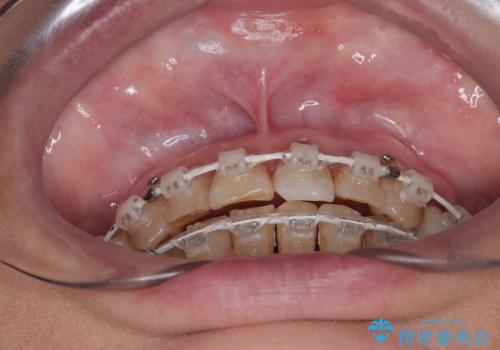

- 長年気にしていた捻れた前歯が欠けたとのことで来院された患者様です。

矯正治療に抵抗があったそうですが、前歯が欠けたことをきっかけに、矯正治療で歯列を整えた上で、セラミッククラウン治療を行う決心が付いたとのことでした。

デコボコが強いため、ブリッジや残根となっている部分のスペースを利用して歯列を整え、変色や欠けている歯をオールセラミッククラウンによる補綴治療を行うこととしました。